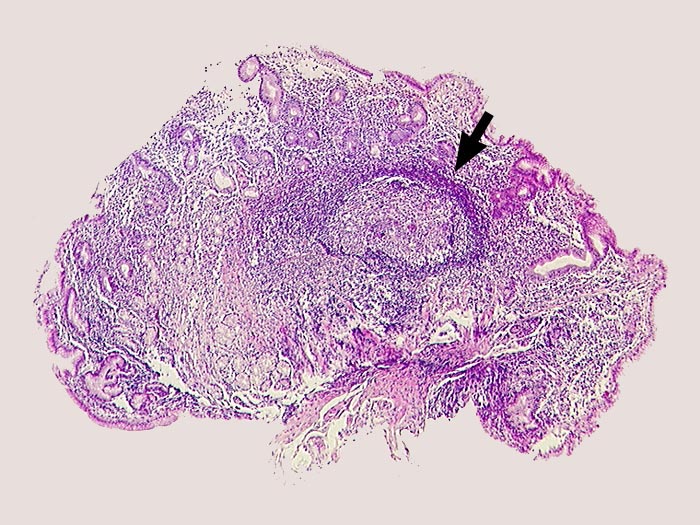

PathoPic ID 1305 - Schwere chronische Helicobactergastritis mit follikulärer Entzündung

Schwere chronische Helicobactergastritis mit follikulärer Entzündung

Dichtes Entzündungsinfiltrat im Stroma.

►

Lymphfollikel mit Keimzentrum.

Helicobacter.

Lymphfollikel kommen charakteristischerweise bei der Helicobactergastritis vor.